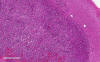

Pathology of the Case: The tumor seems to have a biphasic pattern. In some of the areas, it has the classic features of a neoplastic glial neoplasm (Panel C, D,, & E). These areas show a rather homogenous proliferation of neoplastic glial cells with high-grade nuclei. Note the spongiotic background (Panel E) and this probably are the edematous area demonstrated on FLAIR. In the remaining parts of the specimen, however, there are islands of large, bizarre cells that are well-demarcated (Panel F) from the surrounding tumor with features in Panel C and D. These large cells are characterized by a large variation in size with many of them a centrally located inclusion (Arrow in Panel G) that seems to have pushed the nucelus to an eccentric location. While some of them are binucleated (Arrow in Panel G), multinucleated tumor cells are not common. The nuclei are enlarged, pleomorphic, and with large and eosinophilic nucleoli. These cells are rhabdoid cells. Endothelial proliferation is also present (Arrow in Panel F). There is some necrosis (not shown). On immunohistochemistry, the tumor cells are negative for IDH1-R132H consistent with no mutation. The tumor cells are strongly positive for ATRX consistent with wild-type ATRX. Only occasional tumor cells are positive for p53 indicating no mutation in p53. The Ki67 labeling is much higher, up to about 30%, in the rhabdoid area in comparison to the areas with features of classic high-grade glioma (Panel H & I).

Next generation sequencing panel study and chromosome microarray study were performed in this case with a block containing the rhabdoid changes. There was no loss of SMARCB1(INI1) or SMAECA4(BRG1) were demonstrated by next generation sequencing. Chromosomal changes included gain of chromosome 7, EGFR amplification, CDKN2A/B homozygous deletion, and heterozygous loss of chromosome 10. There was also mutation of TERT promoter. These features were classic for a glioblastoma. The rhabdoid changes stood out distinctly in a background of high-grade glioma.  The significant increase in Ki67 labeling in the rhabdoid area. Both features supported that the rhabdoid component was a high-grade transformation arising from the existing glioma. With all of these features taken into consideration, this is a case of glioblastoma with rhabdoid changes.